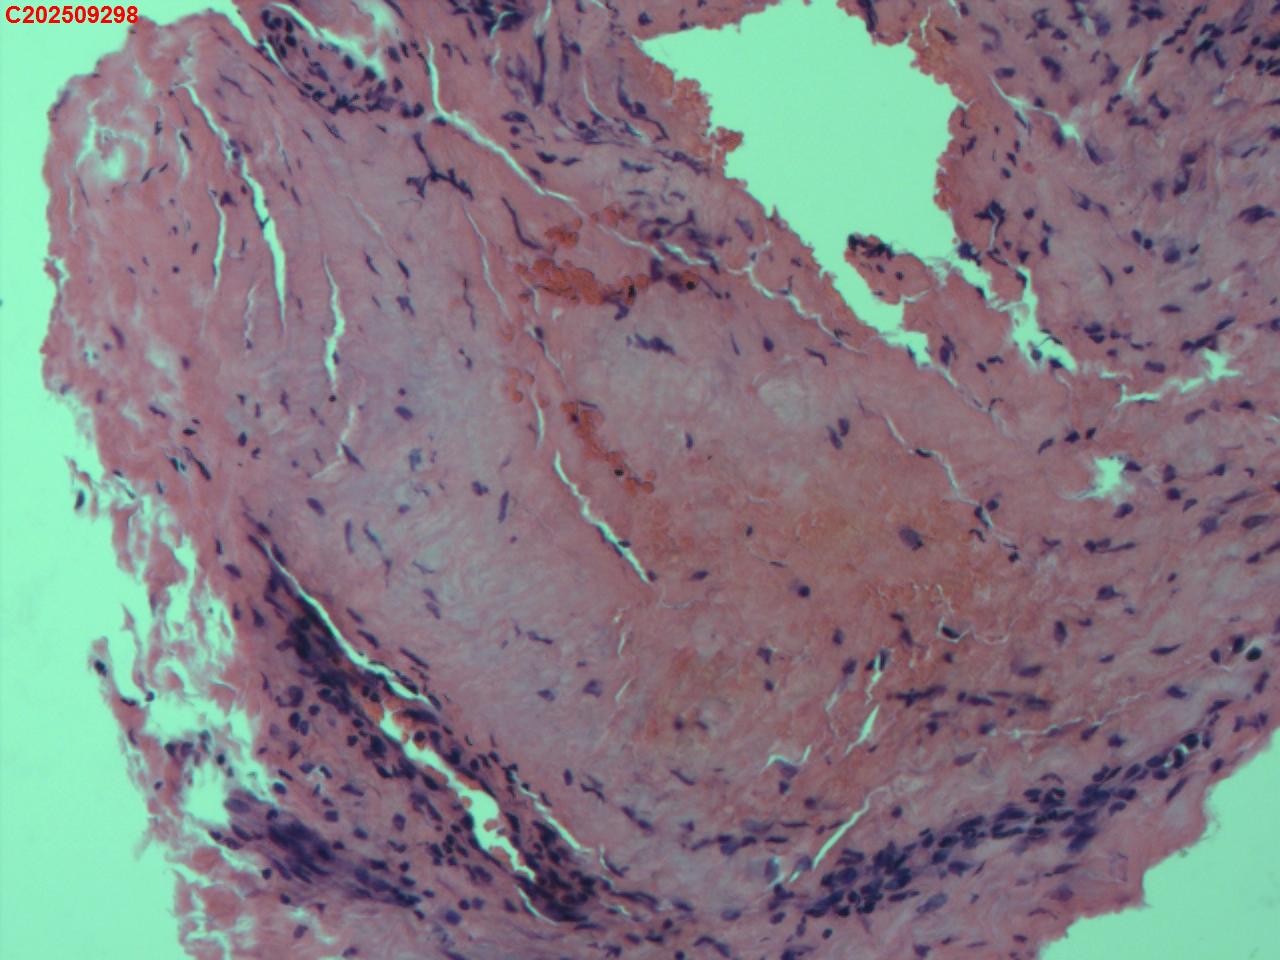

性别

女

年龄

34岁

临床诊断

胸膜结核瘤

一般病史

超声:可见右侧胸膜包裹囊性病变并见胸膜结核瘤。

标本名称

肺穿活检

大体所见

CT:胸部增强CT示右肺病灶局部增大,右侧胸腔结核性胸膜瘤可能。

送检组织·,镜下为炎性细胞和纤维组织。